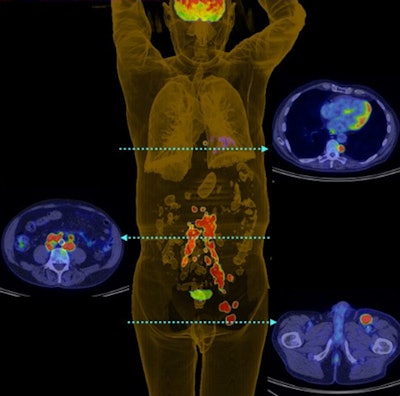

Australian researchers found that FDG-PET scans changed the management plan for more than one-third of patients with Merkel cell carcinoma and altered the disease stage in approximately one in five cases, according to a study in the August issue of the Journal of Nuclear Medicine.

With the information provided by FDG-PET and subsequent changes in treatment plans, overall survival for Merkel cell carcinoma patients was 60% after three years and 51% after five years, according to a team led by Dr. Shankar Siva of the University of Melbourne's department of oncology (JNM, August 2013, Vol. 54:8, pp. 1223-1229).

FDG-PET prowess

FDG-PET scans for tumor staging resulted in a change in treatment for 38 patients (37%), the researchers found. Of the 23 scans that were deemed to have a high impact, 14 (62%) resulted in a change in treatment modality, five (21%) changed treatment intent, and four (17%) changed both treatment modality and radiation therapy technique.

Of the five patients for whom the treatment intent changed, four had their cancer upstaged due to distant metastases and were treated with palliative care. The remaining person was downstaged from suspected but unproven distant metastatic disease and received curative care.

Comparing conventional and PET results showed discrepancies in staging for 22 patients, with PET upstaging 17 patients and downstaging five.